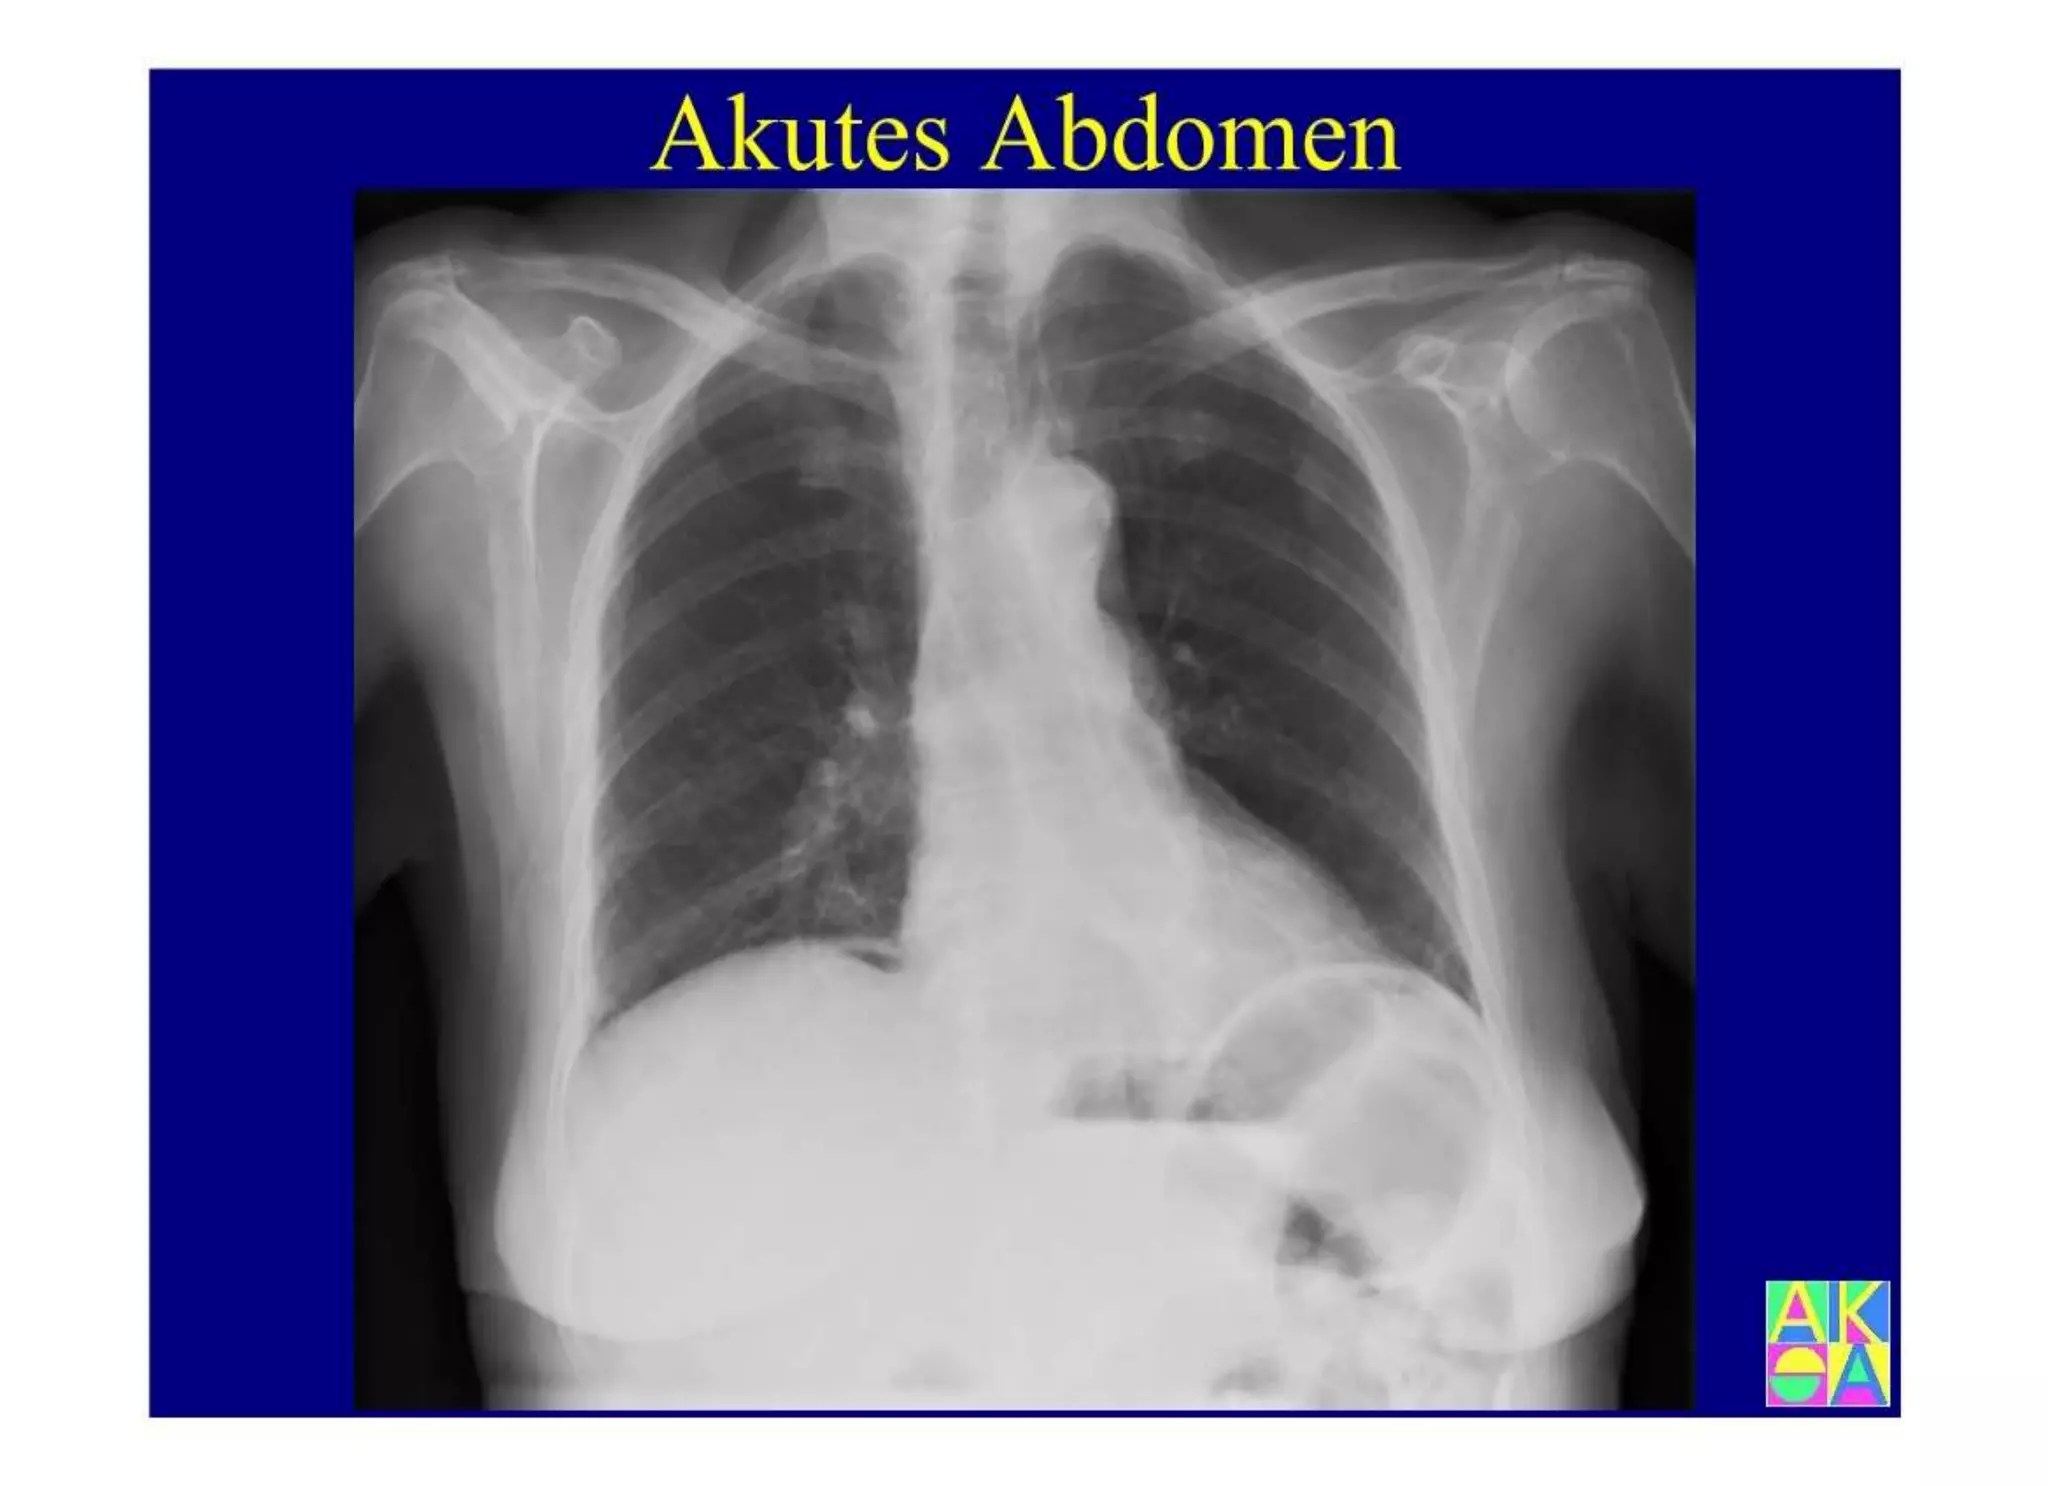

Chronische Enteropathie und Ileus, Dünndarm und Dickdarmdiagnostik, Mechanischer und paralytischer Ileus, Eingeklemmte Darmabschnitte, aufgereihter Bridenileus, und dazu Dickdarmileus, eingeklemmte Hernien, Weitergabeskript